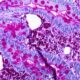

Esta propiedad hace que la fluoresceína sea valiosa en técnicas como la microscopía de fluorescencia y la citometría de flujo. En la microscopía de fluorescencia, se utiliza para marcar y visualizar componentes específicos en muestras biológicas, ya que cuando se ilumina con luz UV, las áreas marcadas con fluoresceína emiten luz verde, lo que facilita la observación y el contraste. En citometría de flujo, se emplea como marcador para etiquetar células y partículas, y su emisión de luz verde se detecta y cuantifica para analizar y clasificar células según la presencia de marcadores específicos.